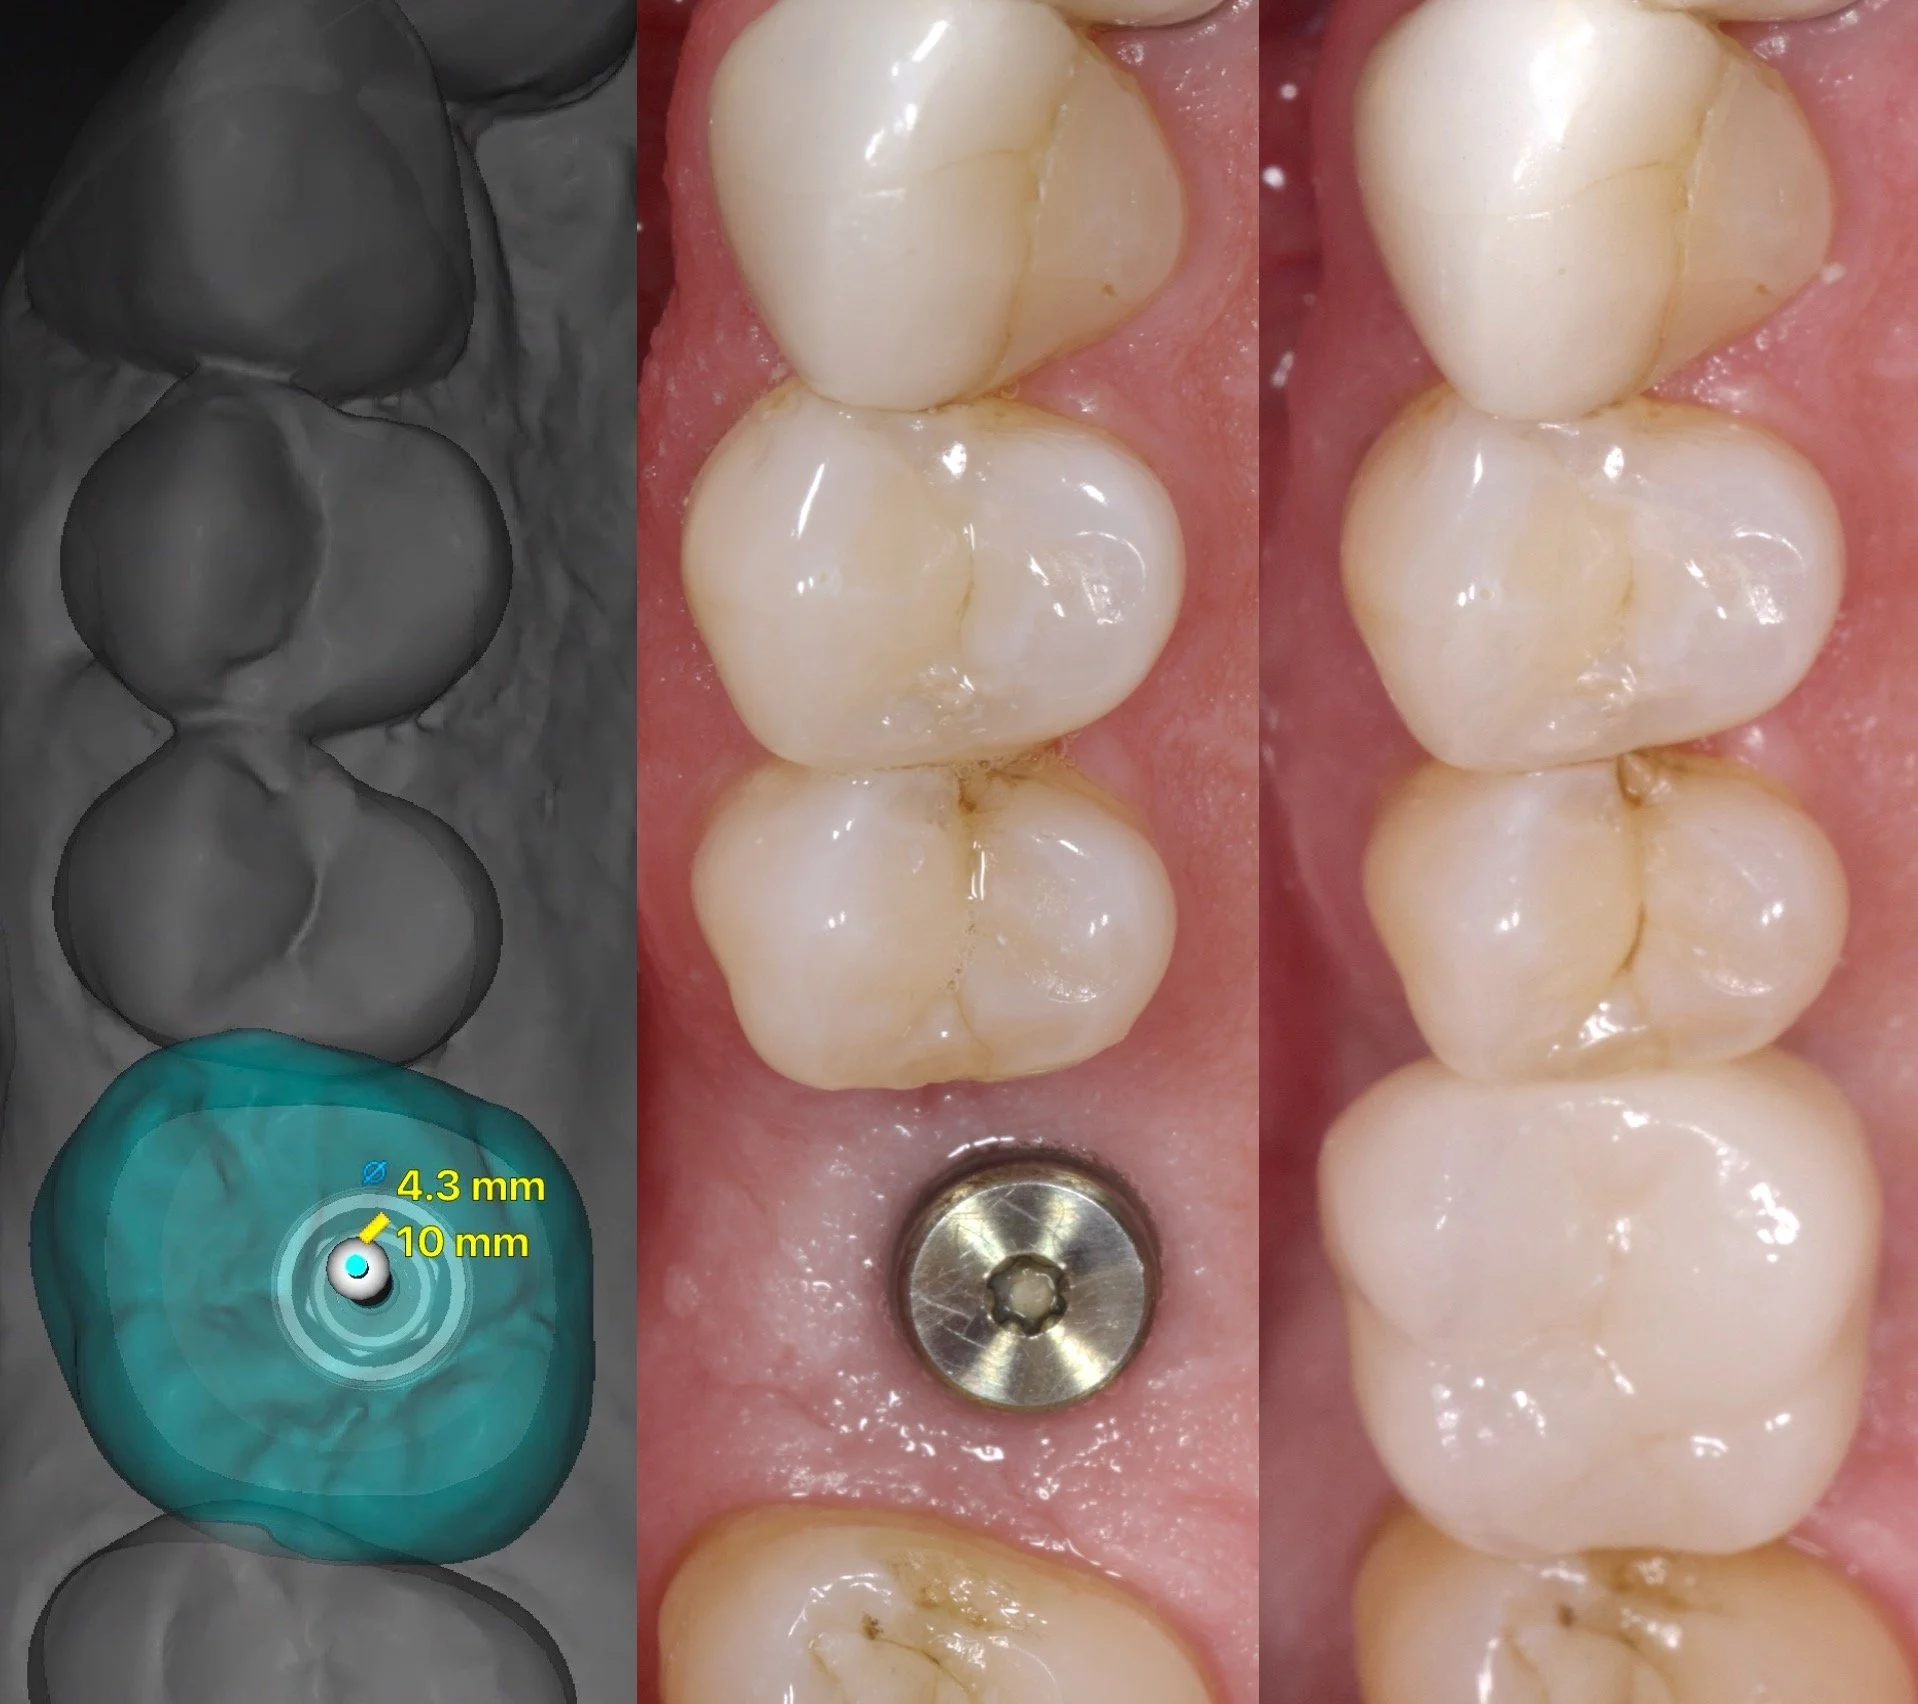

Posterior